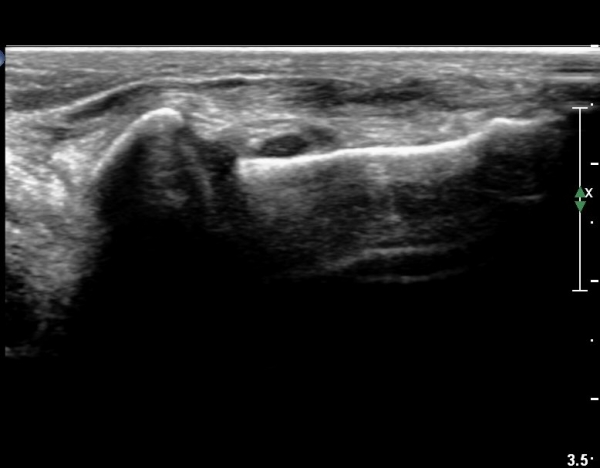

Àü°Åºñ Àδë Á¾´Ü¸é°Ë»ç¿¡¼­ Àü°ÅºñÀδëÀÇ ÆÄ¿­ÀÌ °üÂûµÇ°í(»çÁø 6,7)

ºÎÇÏ°Ë»ç ½Ã °Å°ñ°ú ºñ°ñÀÌ  °úµµÇÏ°Ô ¹ú¾îÁö´Â °ÍÀÌ °üÂûµÈ´Ù(÷ºÎµ¿¿µ»ó 2)

Á¾°ñ ÀÔ¹æ°ñ Àδë Á¾´Ü¸é°Ë»ç¿¡¼­ Á¾°ñ ÀÔ¹æ°ñ ÀÎ´ë  ÆÄ¿­ÀÌ °üÂûµÇ°í(»çÁø 6,7)

ºÎÇÏ°Ë»ç ½Ã Á¾°ñ°ú ÀÔ¹æ°ñ  °úµµÇÏ°Ô ¹ú¾îÁö´Â °ÍÀÌ °üÂûµÈ´Ù(÷ºÎµ¿¿µ»ó 3)